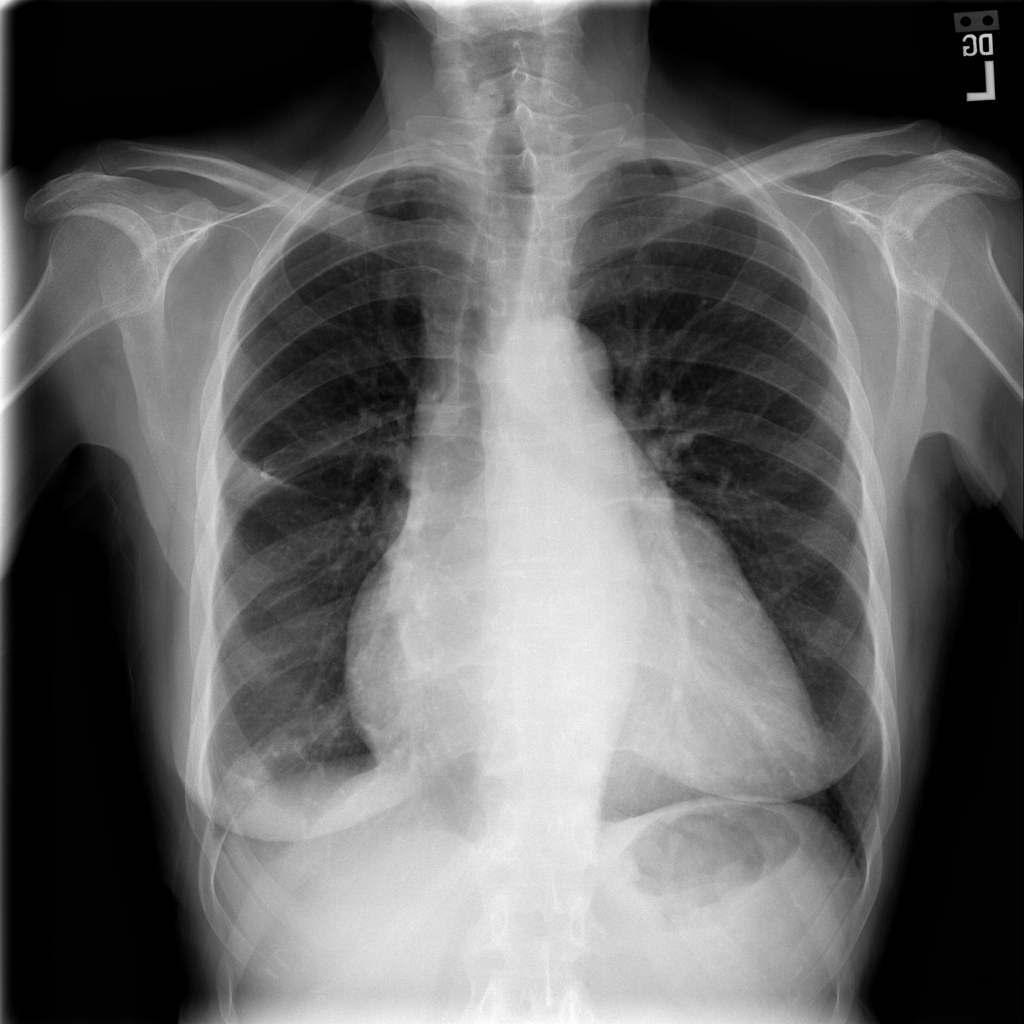

PAT-3384 · IMG-000Cardiomegaly

PAT-3384 · IMG-000

AP